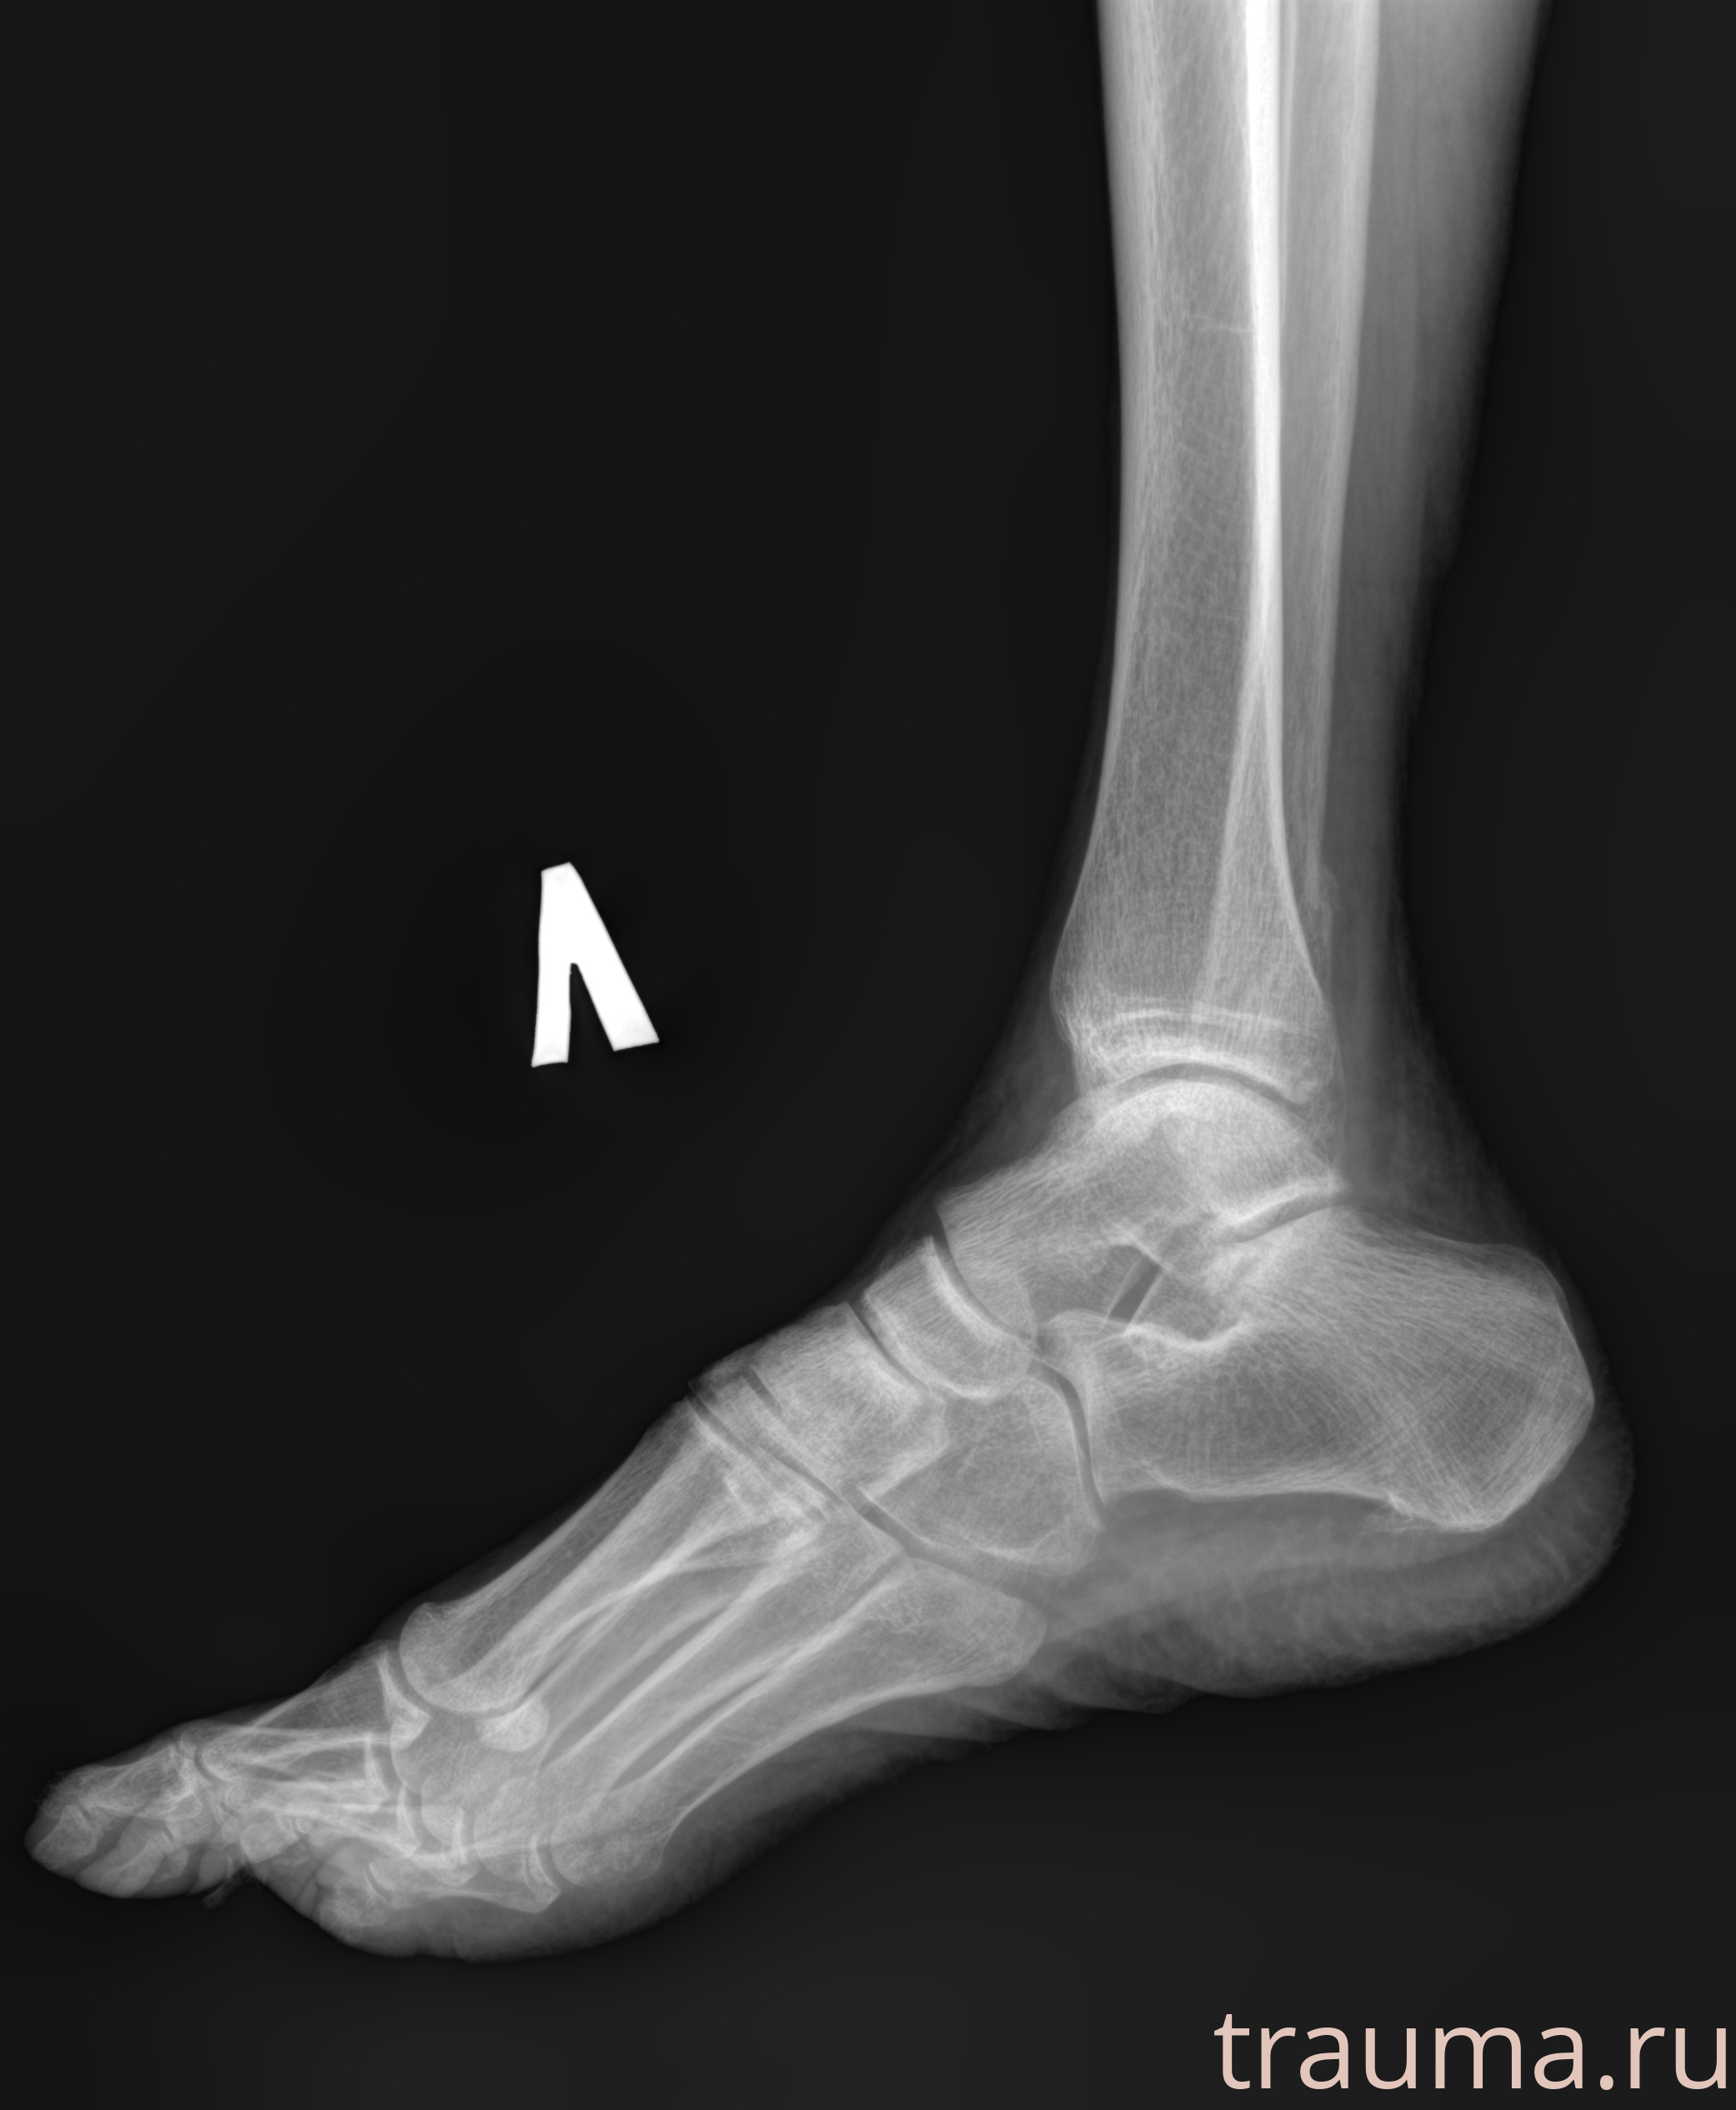

Рентгенограммы

Рентген на дому: по вашему адресу приезжает врач-рентгенолог, травматолог-ортопед с мобильным рентгеновским аппаратом, проводит диагностику травмы или заболевания, делает необходимые рентгенограммы, дает рекомендации по дальнейшему лечению. Получить качественные снимки в домашних условиях возможно благодаря уникальной методике, разработанной МосРентген Центром для института  Склифосовского

Яркость: 1   Контраст: 1   Инвертировать: 0 Увеличение: 1

Перетаскивайте мышь вверх/вниз для контраста, влево/право для яркости. Прокрутка колесом изменяет масштаб. Нажмите Сбросить для возврата к исходному изображению. При увеличении держите мышь в той области, которую хотите рассмотреть.